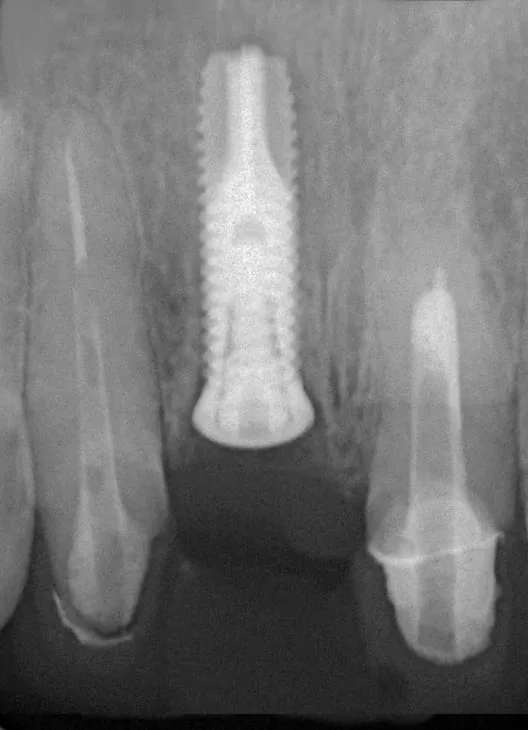

左上兩顆門牙,有牙套不密合之情況。 經仔細評估後,決定拔除並立即植牙(即拔即種,圖2);

(圖2: 拔除右上門牙並立即植牙)